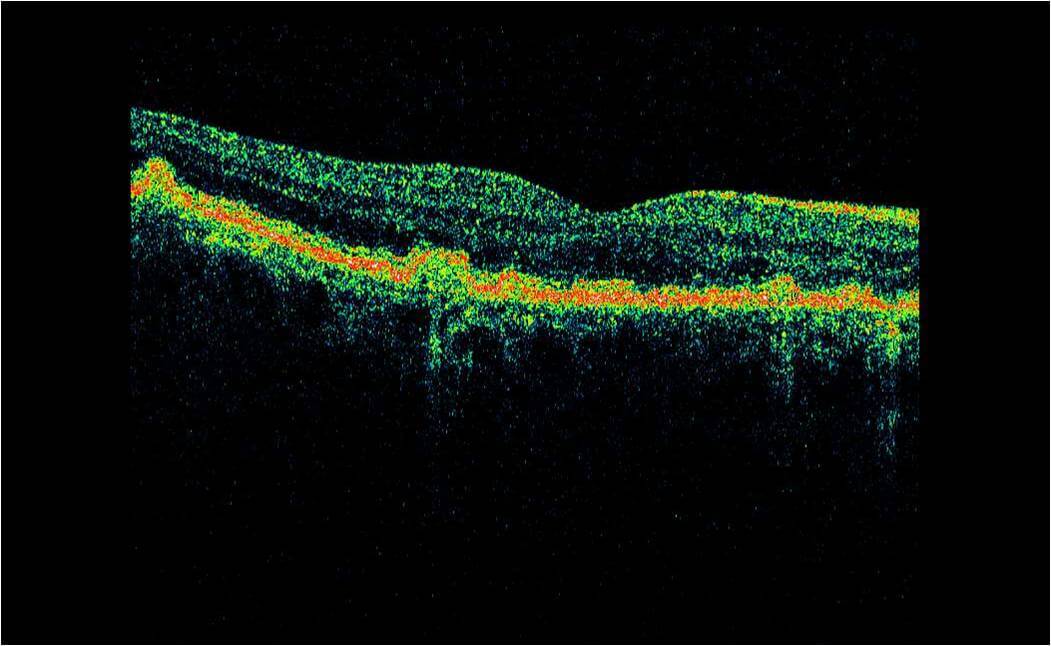

Optical Coherence Tomography (OCT) is an advanced eye scan, similar to ultrasound. The OCT uses light rather than sound waves to illustrate the different layers that make up the back of the eye. Within 2 seconds, the OCT takes over 30,000 individual scans of the back of the eye and this is used to produce a 3D image of the retina and optic nerve. The scan gives an accurate cross-sectional map through the retina and allows examination of the back of the eye in incredibly fine detail.

The OCT also captures a digital photograph of the surface of the eye at the same time, and this can then be cross-referenced with any areas of concern.

The scan shows us beneath the surface of your retina, so we can see and better understand the very fine changes which can be indications of something unhealthy or abnormal.